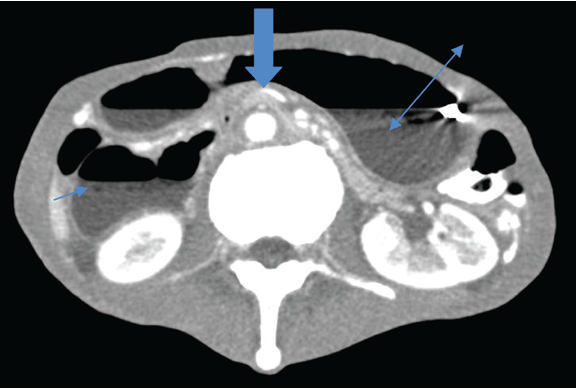

A 64-year-old schizophrenic elderly male was admitted in Singapore government hospital for epigastric pain of 1 day duration associated with a two-day history of vomiting. The character of the vomitus was uncertain. He had lost 30–40 kg of weight over several months. The patient denied postprandial pain and had no previous similar episode. He had no past history of surgery and was not on any psychiatric medication. The patient had paranoid schizophrenia but was never compliant with medications. He lived alone and had persecutory thoughts. He was suspicious of people around him and barred all windows and rooms. He also mentioned cameras watching him and “people” want to harm him. He refused to go out and consumed mainly instant noodles for several years. One month before this admission, he was admitted for hypoglycemia secondary to poor oral intake and incidentally had low calcium and vitamin D deficiency. His vital signs were stable on admission. He appeared comfortable but was severely cachectic with a body mass index of 10.9 kg/m2 (weight 34.4 kg, height 178 cm). The abdomen was scaphoid, distended and tender over epigastric area with no sign of peritoneal irritation and succussion splash was positive. Per rectal examination was unremarkable. Initial laboratory studies were largely unremarkable besides the elevated total white, low creatinine and urea. Supine and erect plain abdominal radiograph showed a grossly distended stomach and collapsed bowel distally. (Figure 1) In view of the distended abdomen, positive succession splash and dilated stomach on abdominal radiograph, our initial impression was gastric outlet obstruction. Patient was kept nil by mouth and nasogastric tube was inserted to maintain gastric and duodenal decompression. Nasogastric tube immediately aspirated 2.2 liters of bilious fluid. Upper gastrointestinal series showed distended stomach and duodenum to the level of mid third part, where an abrupt cut-off occurred. (Figure 2) To determine the aetiology, contrast-enhanced computed tomography (CT) scan of the abdomen was arranged and the third portion of the duodenum was clearly ‘pinched’ by the abdominal aorta and the superior mesenteric artery. The aorta-SMA angle was 4 degrees and the aortomesenteric distance measured 5.6 mm. (Figure 3) (Figure 4) In addition, CT scan also revealed obvious reduction of the intra-abdominal fat. There was no free intraperitoneal air. Based on the history, examination and imaging findings, we diagnosed SMA syndrome. Endoscopic guided insertion of nasojejunal tube was performed for enteral feeding as patient was unable to tolerate any oral intake due to duodenal obstruction. (Figure 5) However, the patient was not cooperative with nasojejunal tube feeding. Subsequently, he developed hypoglycemia, hypokalemia and hypotension that was refractory to resuscitation. Consciousness deteriorated and the patient passed away. | ||||||

Superior mesenteric artery syndrome was first described by Austrian Professor Carl Freiherr Von Rokitansky in 1861. [3] Later Wilkie published the first comprehensive case series of 75 patients with what he initially called “duodenal ileus”, 64 of who underwent duodenojejunostomy. Wilkie’s detailed anatomical, clinical and pathophysiological description of extrinsic compression of third portion of duodenum by the superior mesenteric artery has become a common eponym for SMA syndrome. [4] Subsequently, a variety of other names have been used such as chronic cast syndrome and arteriomesenteric duodenal compression syndrome. [5] [6] Superior mesenteric artery originates acutely from the abdominal aorta behind the neck of the pancreas at the level of first lumbar vertebra and travels caudally into the root of mesentery. The transverse portion of the duodenum crosses anterior to the third lumbar vertebra and was separated from the superior mesenteric artery by the retroperitoneal fatty tissue. The normal angle between abdominal aorta and the superior mesenteric artery is 25–60° and the aortomesenteric distance is around 10–28 mm. [7] [8] Such relationship correlates with body mass index. [2] Pathophysiological loss of retroperitoneal and paraduodenal fats can result in aortomesenteric distance less than 8 mm and aorto-SMA angle of 22° or less, resulting in duodenal ‘clamping’. Such pathophysiology can be seen in chronic wasting disease, catabolic state, anorexia and malabsorption. Surgical interventions can occasionally alter the anatomical relationship, jeopardizing the aortomesenteric angle and resulting in SMA syndrome (e.g., scoliosis surgery, aortic aneurysm repair, bariatric surgery). [1] [5] The SMA syndrome can present acutely or chronically with signs and symptoms of proximal gastrointestinal tract obstruction (i.e., nausea, vomiting, weight loss, sense of repletion and postprandial abdominal distension). Such presentations, however, are nonspecific to SMA syndrome and diagnosis is frequently delayed. Henceforth, a high index of suspicion is required and a comprehensive investigation is recommended to rule other conditions that are common and has different treatment implication including pancreatitis and peptic ulcer disease. [9] Upper gastrointestinal series, contrast-enhanced computed tomography (CT) scan, magnetic resonance angiography (MRA), ultrasound (US) and endoscopy are modalities that can be utilized to establish diagnosis. Our patient had upper gastrointestinal series that revealed a classical dilated proximal duodenum with abrupt contrast cut-off at the transverse portion of duodenum. Computed tomography scan of abdomen with contrast can clearly demonstrate the obstruction site, determine the aetiology of the obstruction and allows evaluation of aortomesenteric angle and aortomesenteric distance, both of which are sensitive measures of diagnosis. An aortosuperior mesenteric artery angle of less than 25° and aortomesenteric distance less than 8 mm are highly suggestive of SMA syndrome. [9] In our patients, both parameters were reduced with angle and distance of 4° and 5.6 mm, respectively. Upper endoscopy can be used to rule out stenosing lesions in the duodenum. With the advent of noninvasive radiological studies, conventional arteriography is rarely needed in the workup of SMA syndrome except in cases where diagnosis is not clear. The treatment of SMA syndrome can be either conservative or surgical. Patients with SMA syndrome initially require nasogastric tube insertion for gastrointestinal decompression, fluid resuscitation, correction of electrolyte abnormalities and early nutritional support. Nutritional support aims to promote body weight gain and restore the retroperitoneal fat tissue with subsequent increase in aortomesenteric angle and reduction in duodenal obstruction. Nasojejunal tube that is placed distal to the obstruction allows enteral administration of nutrition. Parenteral nutrition may be an alternative but it is not without its associated complications. Notably, patient should be monitored for refeeding syndrome during nutritional rehabilitation as these patients are malnourished and are susceptible to electrolyte and fluid shifts. Duration to achieve symptomatic improvement is variable in conservative nutritional treatment and has been documented to range from 2–169 days. [1] Patients with shorter history of SMA syndrome have higher success rate with conservative management. On the other hand, those with more chronic history have a prolonged hospital stay with low success rates of conservative treatment alone and surgery after a period of refeeding and weight gain is indicated. [8] Several surgical options have been proposed to resolve or bypass the duodenal compression including Strong’s procedure (caudal mobilization of duodenojejunal flexure by division of ligament of Treitz), gastrojejunostomy and duodenojejunostomy. The advantage of Strong’s procedure includes maintaining bowel integrity, easier and quicker to perform and less invasive and is a safer procedure. [9] However, Strong’s procedure has high failure rate of 25% and presumably due to difficulty in mobilizing the duodenum with interference from intra-abdominal adhesions and the short vessels of the inferior pancreaticoduodenal artery. Gastrojejunostomy can decompress the stomach adequately but it does not resolve the duodenal obstruction and the patient can have persistent symptoms. Furthermore, such bypass operation can cause blind loop syndrome, gastric bile reflux and peptic ulceration that necessitate second operation (i.e., duodenojejunostomy). Duodenojejunostomy is the surgical treatment of choice and can be performed with or without division of fourth portion of the duodenum. It has a reported a success rate of 90%. [10] | ||||||